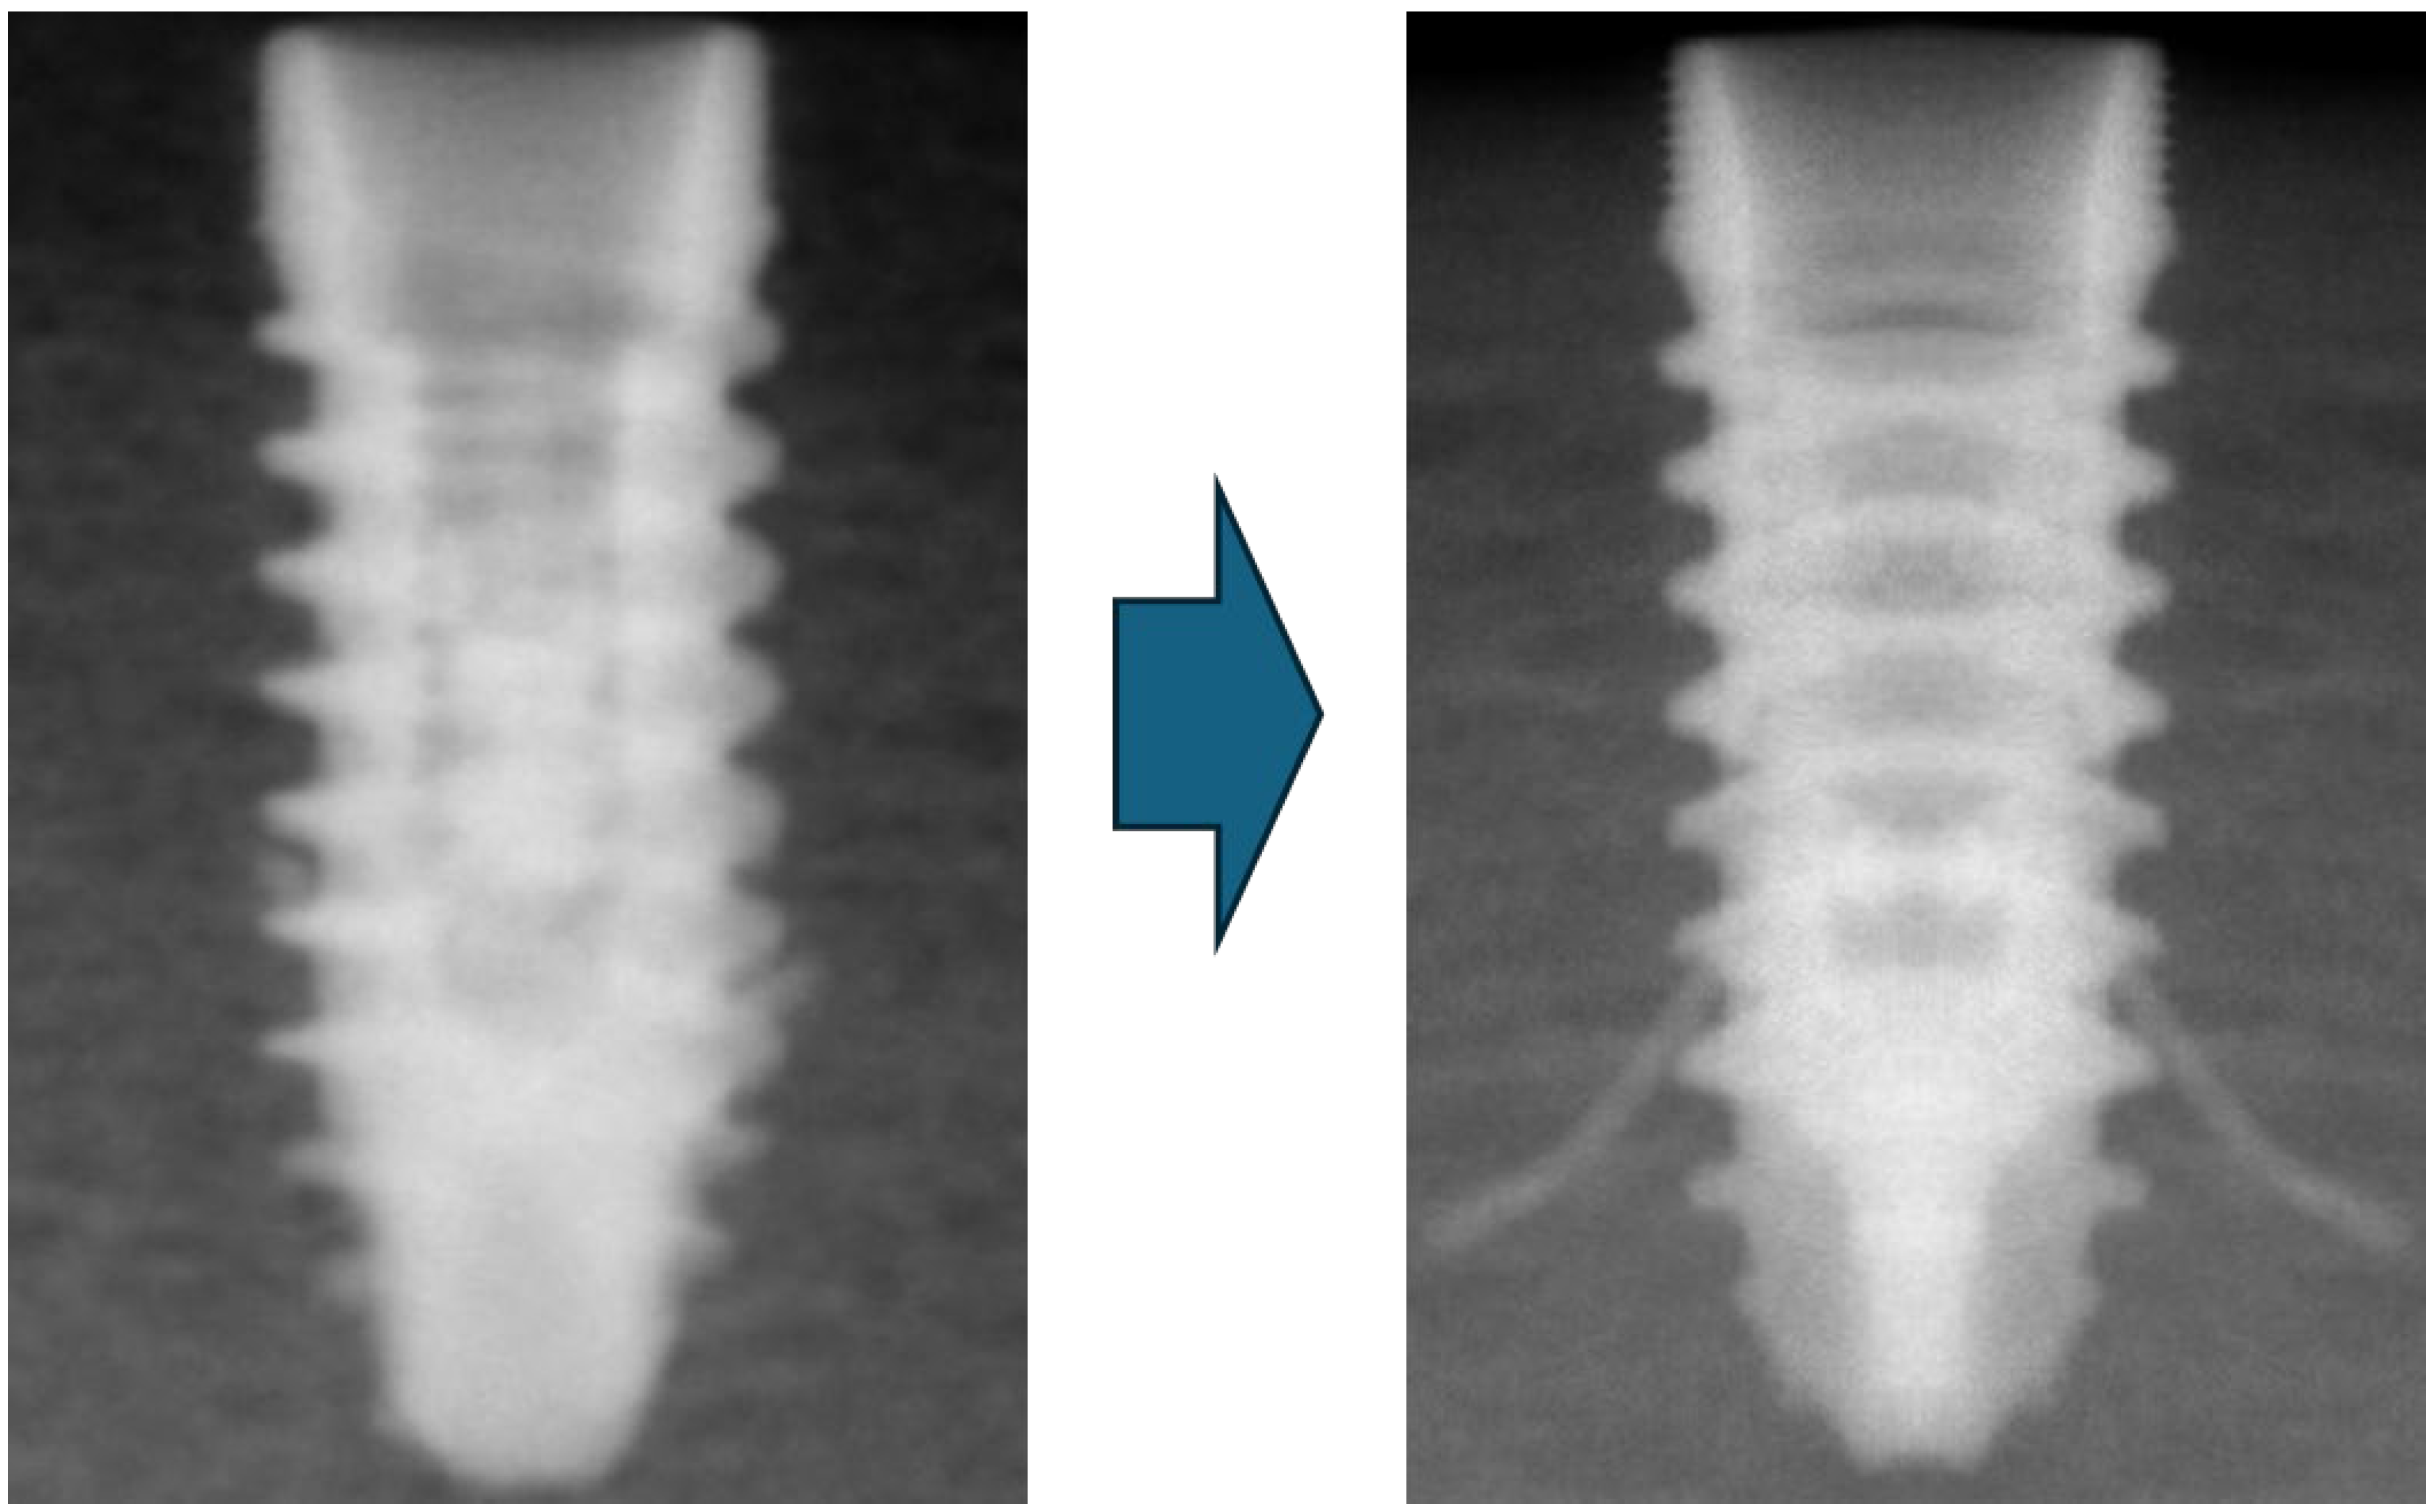

We confirmed the correct position of the implant with portable X-ray equipment before deploying the barrettes. In case any implant was not in a perfect position, it was readjusted and confirmed via a new X-ray study before any further steps were taken (Figure 4).

Figure 4.

X-ray picture of the dental implant inserted before and after the barrettes were deployed.